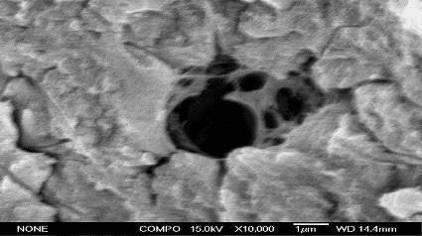

. Исследование морфологии огнестрельных переломов пластинчатых и

трубчатых костей методом атомно-силовой микроскопии (25 образцов).

. Исследования тонкой структуры костного матрикса области регенерата

методом сканирующей электронной микроскопии (10 образцов).